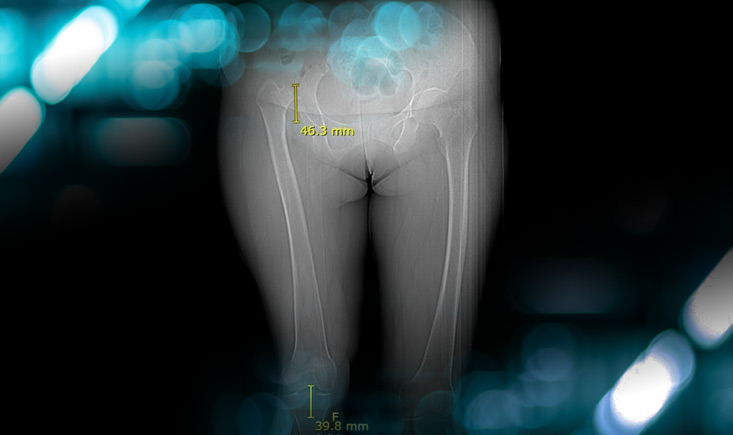

Pre-operative X-rays and CT-scan

Management of a hip dysplasia in a middle-aged woman:  Pre-operative X-rays and CT-scan

How would you grade this dysplasia?

• ✔️Crowe IV